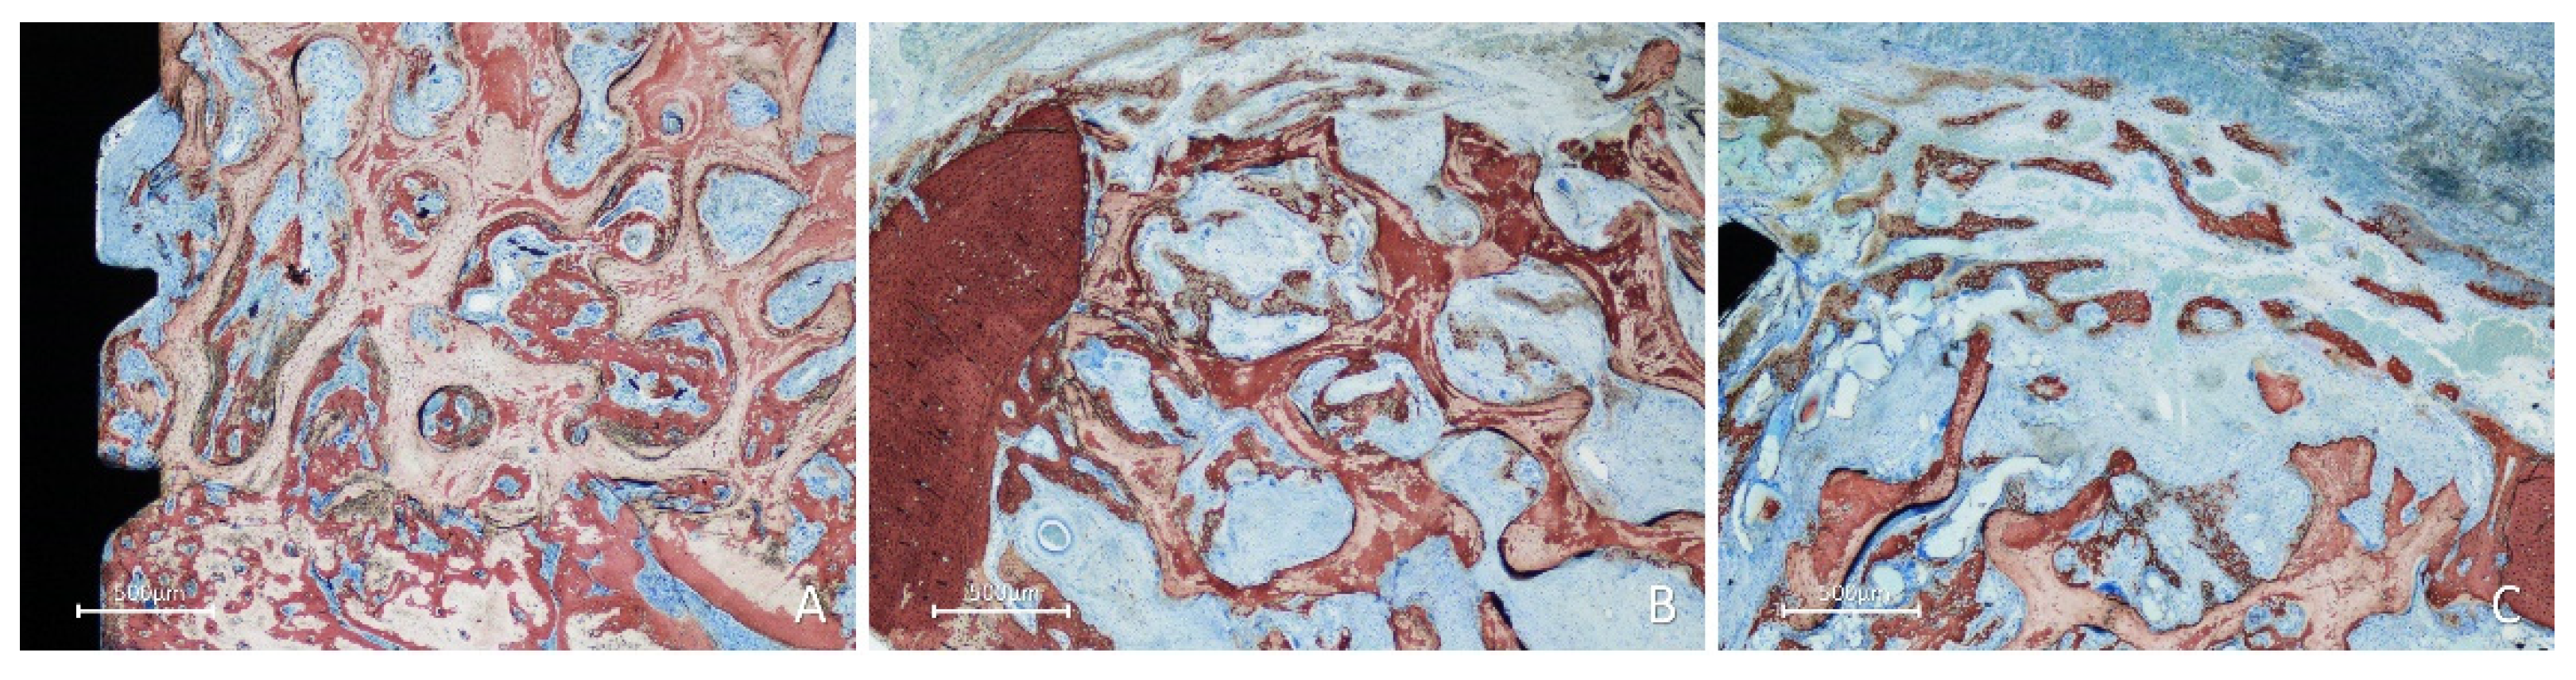

In the inlay group, after 2 weeks of healing, the position within the self-contained defect allowed the presence of multiple sources of new bone. Bone formation was observed in the cortex of the mandible, perforations of the fixation screw (Figure 6A), and lateral aspects of the defect bone walls (Figure 6B). At the periphery of the defect, new bone formed from the cortical layer, growing over the top of the graft and underneath the collagen membrane (Figure 6B,C), closing the defect.

Figure 6. Photomicrographs of ground sections showing healing aspects at inlay graft sites after 2 weeks. Bone formation was observed: A, from the cortex of the mandible and the perforations of the fixation screw; B, from the lateral walls of the defect; C, from the lateral walls of the defect growing over the top of the graft and underneath the collagen membrane. Stevenel’s blue and alizarin red stain.